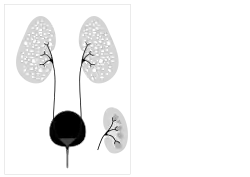

Autosomal recessive polycystic kidney disease (ARPKD) is the recessive form of polycystic kidney disease. It is associated with a group of congenital fibrocystic syndromes.[5] Mutations in the PKHD1 (chromosomal locus 6p12.2) cause ARPKD.[6][7]

Symptoms and signs include abdominal discomfort, polyuria, polydipsia, incidental discovery of hypertension, and abdominal mass.[1] The classic presentation for ARPKD is systemic hypertension with progression to end-stage kidney disease (ESKD) by the age of 15. In a typical presentation, a small number of individuals with ARPKD live to adulthood with some kidney function; but with significant deterioration in liver function.[8] This outcome is postulated to result from expression of the polycystic kidney and hepatic disease gene PKHD1, which is located on chromosome 6p.[9] In severe cases, a fetus will present with oligohydramnios and as a result, may present with Potter sequence.[10]

Ultrasonography is the primary method to evaluate autosomal recessive polycystic kidney disease, particularly in the perinatal and neonatal stages.[3]